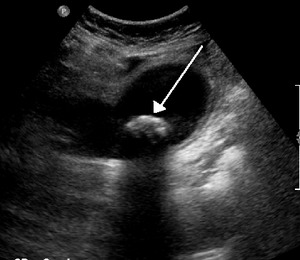

Biliary colic is often related to a stone in the gallbladder

Diagnosis is guided by the person's presenting symptoms and laboratory findings. The gold standard imaging modality for the presence of gallstones is ultrasound of the right upper quadrant. There are many reasons for this choice, including no exposure to radiation, low cost, and availability in city, urban, and rural hospitals. Gallstones are detected with a specificity and sensitivity of greater than 95% with ultrasound.[12] Further signs on ultrasound may suggest cholecystitis or choledocholithiasis.[13] Computed Tomography (CT) is not indicated when investigating for gallbladder disease as 60% of stones are not radiopaque.[13] CT should only be utilized if other intra-abdominal pathology exists or the diagnosis is uncertain.[14] Endoscopic retrograde cholangiopancreatography (ERCP) should be used only if lab tests suggest the existence of a gallstone in the bile duct.[13] ERCP is then both diagnostic and therapeutic.